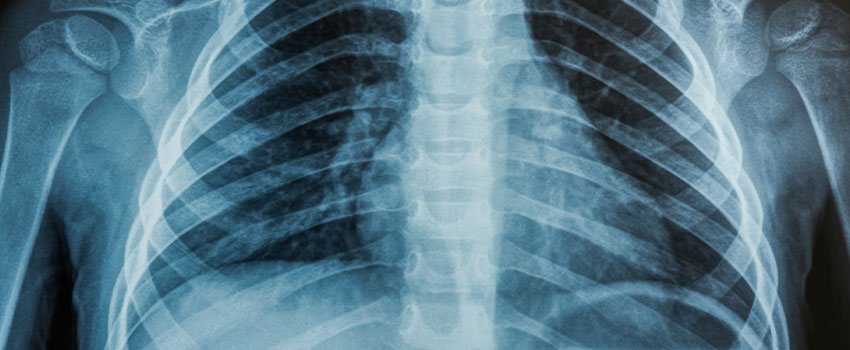

Our team is the best in the area when it comes to diagnosing and treating injuries and illnesses. We start with a full visual examination, and we can run blood tests and rapid tests to figure out what is wrong or what is causing you pain. In addition to these tests,...